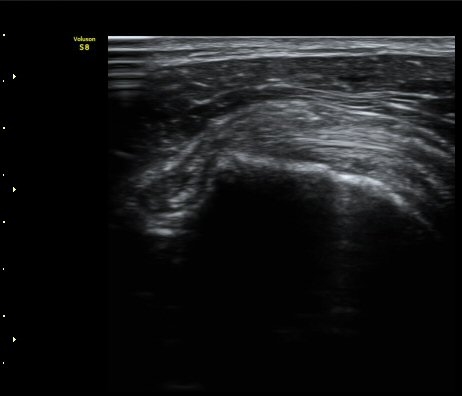

¿ÜȸÀüÀÇ Á¦ÇÑÀ¸·Î °ß°©ÇϱٰÇÀÌ ¼öÆòÀ¸·Î °üÂûµÇÁö ¸øÇϰí À̵ιڱ٠ǥÃþ¿¡

¼®È¸È­ À½¿µÀÌ °üÂûµÊ(±×¸² 3)